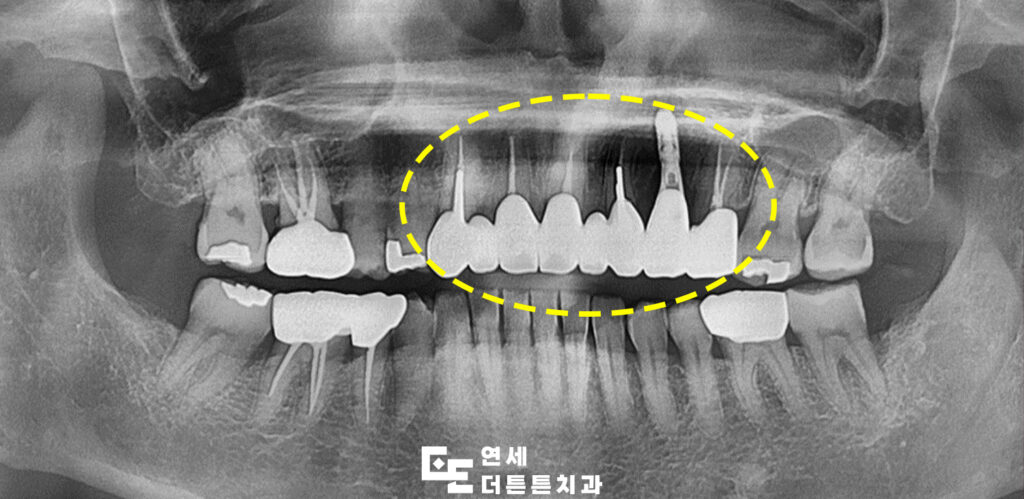

이에 기존 보철물을 모두 제거한 뒤 도봉동치과 앞니치료 계획에 따라 신경치료가 필요한 치아는 선행 치료를 진행하고 이후 재수복을 결정하게 되었습니다.

이미 치아가 상실된 부위에는 임플란트 식립을 먼저 시행하였으며 전반적인 조화를 고려해 지르코니아 브릿지로 최종 보철을 완성하였습니다.